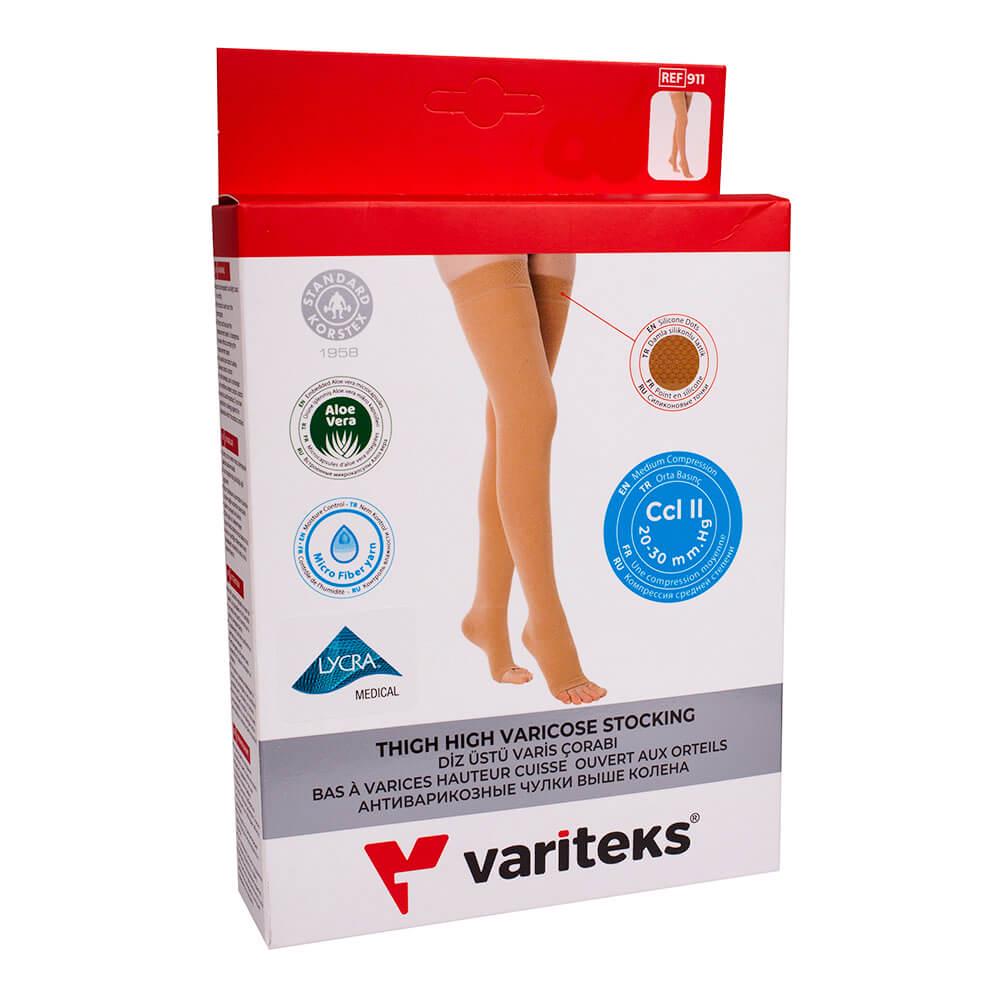

- Ортопедические изделия

- Домашняя аптека

- Медицинские приборы